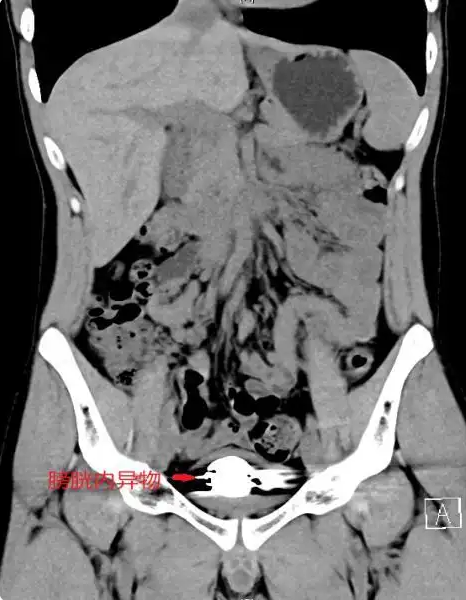

“胆子真大!”湖南22岁男子尿急尿痛长达1年,才去医院就诊。检查后发现他膀胱里竟藏有50粒,直径约5毫米的磁珠,表面已经形成钙化外壳。网友:这东西他是怎么搞进去?   7月4日报道,湖南长沙一名22岁的男子被紧急送往医院救治。男子从一年前开始就感觉小便非常频繁,并且在尿急的时候,还会感觉到剧烈的疼痛。可男子觉得自己这么年轻前列腺总不能出问题,更主要的是面子在这里,如果让好兄弟知道自己那里出了问题,这辈子不就抬不起头。   所以男子一直没有在意,后来渐渐的也就习惯了。可是随着时间的推移,男子的不适感感觉越来越强烈,甚至已经严重影响了自己上厕所,男子实在疼痛难忍,所以什么也不管了,直接去医院检查。   医生也就赶紧让男子去拍了片,拿到结果的医生一看,顿时就紧皱眉头。因为男子膀胱附近有密密麻麻不少的圆球状物体。

医生知道这是造成男子疼痛的主要原因,在进行手术时,医生发现这些是一颗颗的小磁珠,互相难舍难分不说,主要是表面都已经钙化,并且牢牢的吸附在膀胱壁上,稍微有点不慎,都会对男子造成极大的影响。   医院赶紧叫来多个科室会诊,经过两个小时的手术,终于将男子体内所有的磁珠取出。术后男子上厕所的时候也没有感受到有异物的感觉,也获得了前所未有的轻松。当医生问到这些磁珠是如何进入男子体内的时候,男子只是红着脸,不发一言,医生也顿时明白男子的意思了,并没有过多的提问。   磁珠这个东西早在几年前,都有不少新闻科普危险性有多高了。几年前磁力珠是孩子们几乎人手一个的玩具,可是在玩的时候,很多孩子都不小心误食,或者好奇的从其他部位塞入体内。这些磁力珠会通过肠道的运作汇合到一起,在某个部位紧紧的吸附在一起,对人体的危害非常大。   轻则就是导致肠道黏连、穿孔,甚至坏死。重则就是新发感染性休克。像男子这一病例也是被折磨了1年,如果男子仍旧坚持不去医院做手术的话,那么男子迟早会有生命之忧。